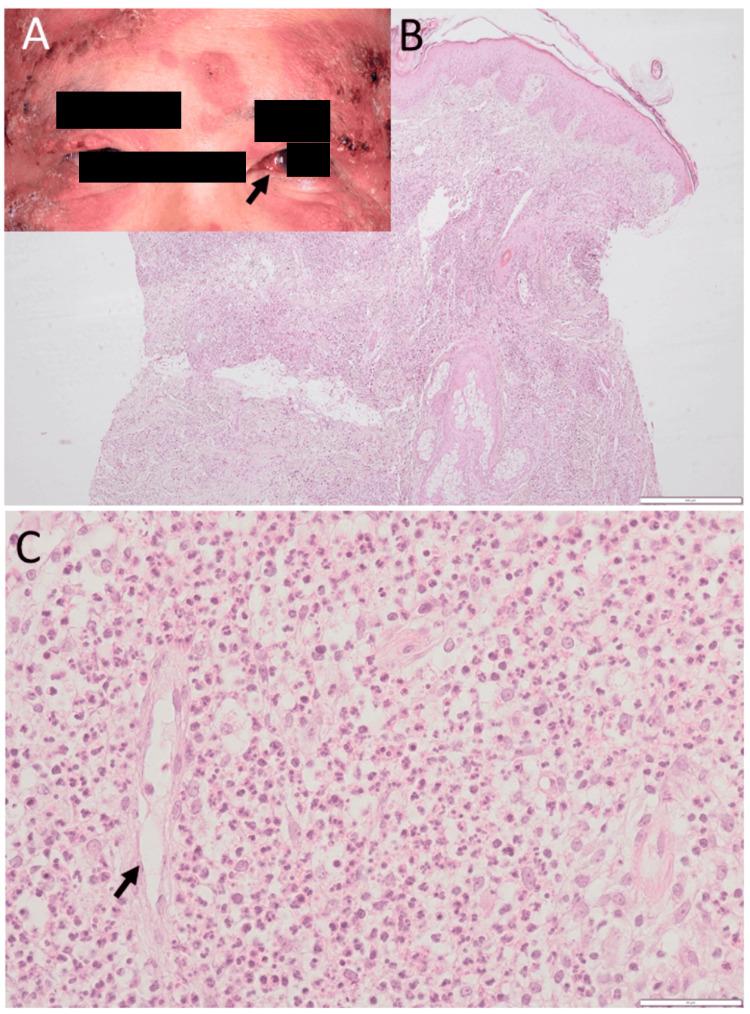

Pyoderma gangrenosum is a non-infectious autoimmune disease with skin plaques and ulcers in the entity of neutrophilic dermatosis and may have a background of myelodysplastic syndromes. This study reported a 20-year follow-up of a patient with pyoderma gangrenosum and scleritis who showed chromosomal aberrancy from the initial phase and later in the course developed thrombocythemia. A 51-year-old man presented with widespread indurated erythematous plaques with scaling and pustules on the forehead, bilateral eyelids, and nasal bridge, in addition to nodular scleritis in the left eye and ulcer formation of the plaques in the lower legs. Skin biopsy revealed massive dermal infiltration mainly with neutrophils in the absence of neutrophilic vasculitis. Suspected of myelodysplastic syndromes, bone marrow biopsy was normal, while chromosomal aberrancy, 46, XY, del (20) (q11q13.3), was detected. In the diagnosis of neutrophilic dermatosis, probably of pyoderma gangrenosum, he began to have oral prednisolone 20 mg daily and colchicine 1 mg daily, leading to the subsidence of skin lesions. Four months later, he developed nodular scleritis in the right eye and began to use topical 0.1% betamethasone in both eyes. He was stable with only prednisolone 12.5 mg daily until the age of 55.5 years, when he showed an increase of serum lactate dehydrogenase. The bone marrow aspirate disclosed neither blast cell increase nor atypical cells. The same chromosomal aberrancy was repeatedly detected. One year later, he developed breathing difficulty and underwent tracheostomy. Laryngeal lesion biopsy disclosed squamous cell papilloma with human papillomavirus-6. At 60 years old, he showed marginal corneal infiltration in the left eye, and at 61 years old, hypopyon in the right eye. Platelets tended to increase up to 1000 × 10/µL, and bone marrow examinations were recommended but refused by the patient. At the latest follow-up at 71 years old, he was ambulatory in health and stable with a tracheostomy cannula. In conclusion, pyoderma gangrenosum with scleritis occurred in an undetermined hematological malignancy with chromosomal aberrancy.

坏疽性脓皮病是一种非感染性自身免疫性疾病,属于嗜中性皮病范畴,表现为皮肤斑块和溃疡,可能伴有骨髓增生异常综合征背景。本研究报告了一名患有坏疽性脓皮病和巩膜炎的患者长达20年的随访情况,该患者从疾病初期就出现染色体异常,随后病程中发展为血小板增多症。一名51岁男性,前额、双侧眼睑和鼻梁出现广泛的硬结性红斑斑块,伴有鳞屑和脓疱,此外左眼患有结节性巩膜炎,小腿斑块形成溃疡。皮肤活检显示真皮大量浸润,主要为中性粒细胞浸润,无嗜中性血管炎。怀疑患有骨髓增生异常综合征,骨髓活检正常,但检测到染色体异常,核型为46, XY, del(20)(q11q13.3)。在诊断为可能是坏疽性脓皮病的嗜中性皮病后,他开始每日口服泼尼松龙20 mg和秋水仙碱1 mg,皮肤病变逐渐消退。四个月后,他右眼出现结节性巩膜炎,开始双眼使用0.1%倍他米松滴眼液。在55.5岁之前,他仅每日服用12.5 mg泼尼松龙病情稳定,此时他血清乳酸脱氢酶升高。骨髓穿刺未发现原始细胞增多或非典型细胞。反复检测到相同的染色体异常。一年后,他出现呼吸困难并接受了气管切开术。喉部病变活检显示为伴有6型人乳头瘤病毒的鳞状细胞乳头瘤。60岁时,他左眼出现角膜边缘浸润,61岁时右眼出现前房积脓。血小板计数逐渐升高至1000×10⁹/L,建议进行骨髓检查,但患者拒绝。在71岁的最后一次随访中,他健康状况尚可,带着气管切开套管病情稳定。总之,坏疽性脓皮病合并巩膜炎发生于一种伴有染色体异常的未明确血液系统恶性肿瘤患者。